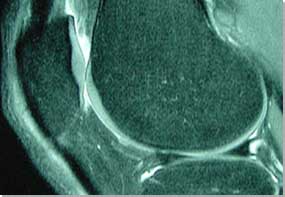

| MR image of the knee - articular

cartilage is shown particularly well. |

Once the radio waves are stopped, excited atoms emit radio signals

received by an antenna (a surface coil in the MRI machine), which are

then measured and processed to form an image using a computer. In the

human body, protons are most abundant in the hydrogen atoms of water.

Thus, MRI images represent the water content in the area of the exam.

The more water present, the more radio signals emitted, and the whiter

the image. All intra-articular structures, including menisci, ligaments

and articulating surfaces, can be visualised in great detail. The indications

for MRI of the knee are difficult to define and depend on the specific

clinical situation and the particular information needed. Routine MR

knee imaging is usually very accurate and helpful diagnostically. MRI is also safe. There are no known side effects to having an MRI